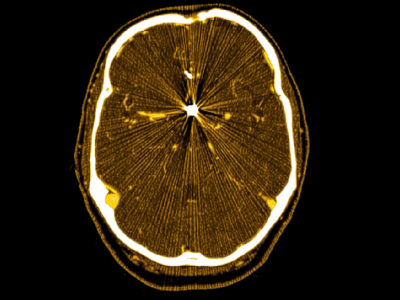

No 1 | Planifier la résection d’une tumeur cérébrale à l’aide des circuits cérébraux